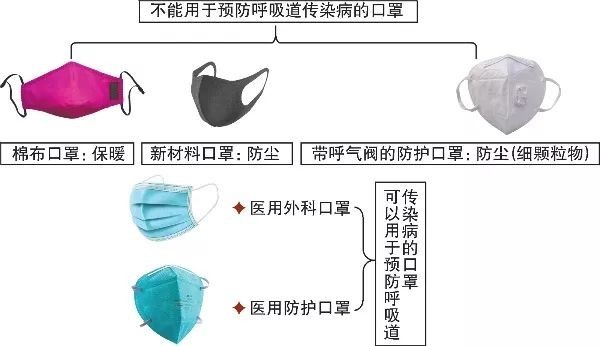

但不是所有口罩都能夠有效阻止新型冠狀病毒,根據中國疾病預防控制中心編著的“新型冠狀病毒感染的肺炎公眾防護指南”可以了解到,普通民眾、公共交通司乘人員、出租車司機、環衛工人、公共場所服務人員等在崗期間,建議使用醫用外科口罩,醫用外科口罩在一定程度可以預防呼吸道感染,有條件且身體狀況允許的情況下,可佩戴醫用防護口罩。而棉布口罩、新材料口罩和帶呼吸閥的防護口罩,無法有效預防呼吸道傳染病。

圖片來自中國疾病預防控制中心“新型冠狀病毒感染的肺炎公眾防護指南”